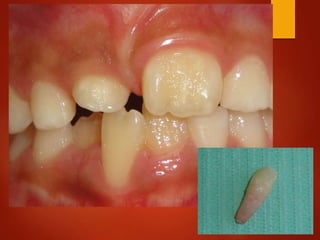

El documento es un registro médico odontológico que muestra las fechas de las visitas de un paciente al centro de salud El Raval, incluyendo exámenes y tratamientos realizados como la extracción de cálculos salivales en abril y mayo de 2012.